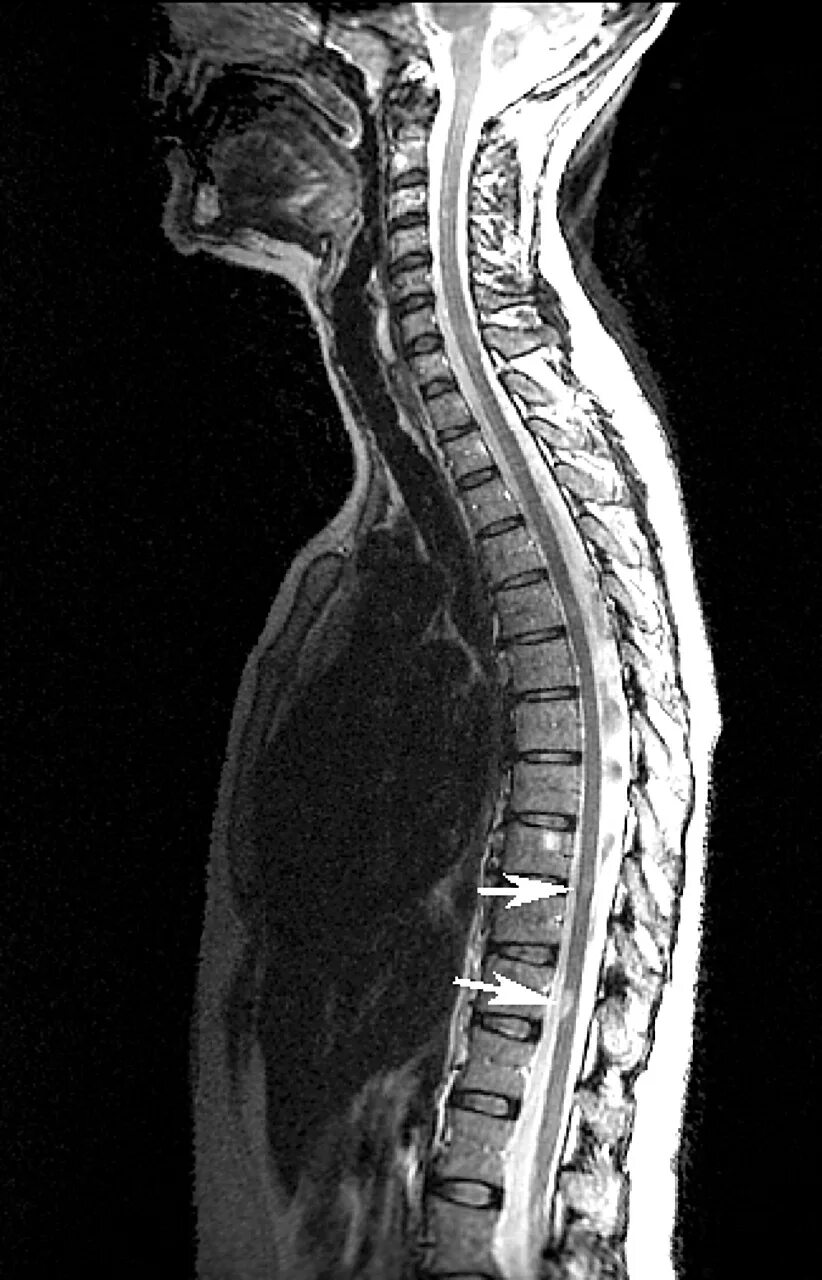

Spine mri